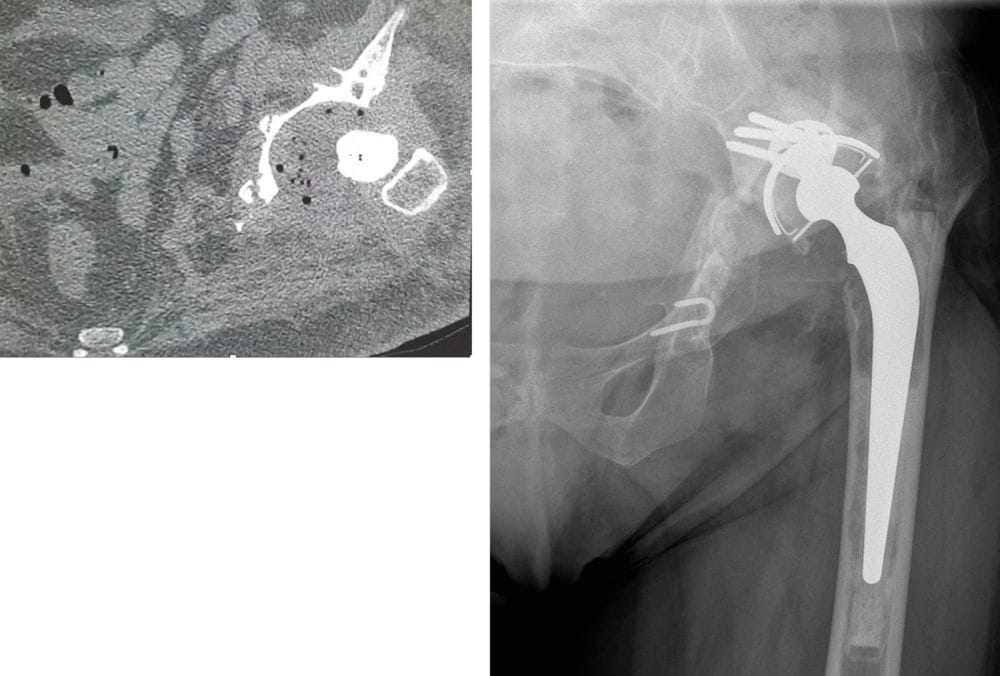

Case report n° 7

82-year-old female Fractured neck of femur while cross-country skiing

- Hemiarthroplasty

- 3 early dislocations

- Single component revision R1 conversion to dual mobility THA

- 2 further episodes of dislocation reduced under GA

- Feels like hip is clicking ever since last dislocation

Two component revision (R2) (Figures 11 & 12)

Infection on D15:

- Debridement, moving parts changed, antibiotics

- Radiography after 1 year

- Walking unrestricted with a stick (has stopped cross-country skiing)